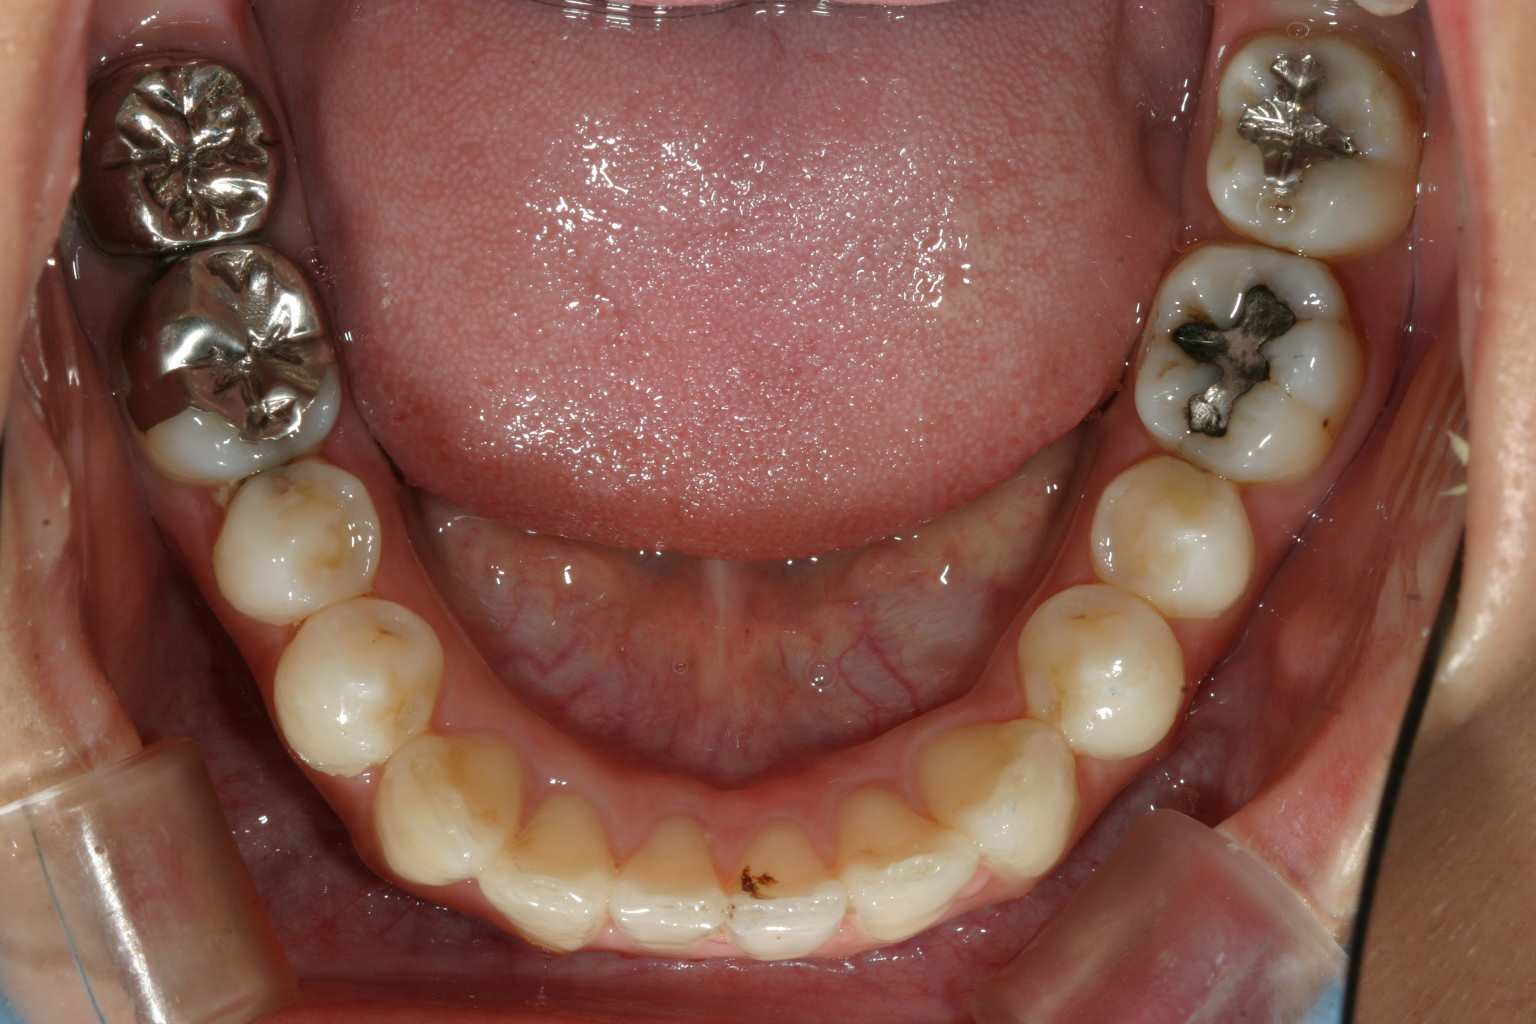

片前歯が飛び出し、又左上の5番目の歯が90度回転しているのが目立ちます。

下顎は少しの叢生が有ります。

前歯が少し歪んでいます。